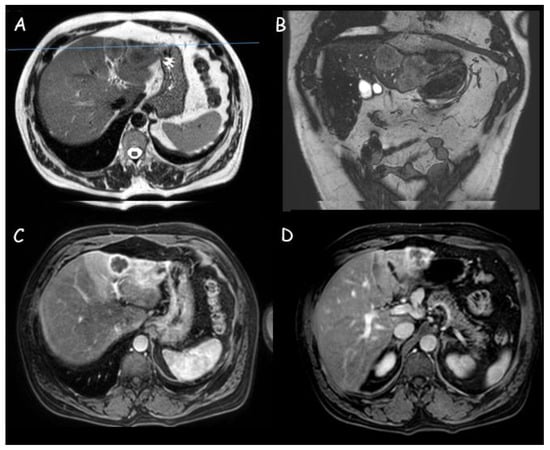

Figure 3.

Magnetic resonance imaging of a 3 cm intrahepatic cholangiocarcinoma in segment III: (A,B) Moderately hyperintense lesion in T2 weighted sequences with weak restriction in diffusion-weighted imaging; (C,D) Peripheral contrast enhancement with perfusional alterations.

MRI and MRCP represent the imaging techniques of choice for CCA diagnosis. It appears as a hypointense lesion on T1-weighted sequences and heterogeneously hyperintense on T2-weighted sequences with a central hypointensity related to the presence of fibrosis (Figure 3 and Figure 4) [42,43]. A target-like image is obtained on diffusion-weighted sequences with increased restricted diffusion in the peripheral zones of the lesion (with diffusion restriction on apparent diffusion coefficient-ADC) and less restricted diffusion in the central area (low-signal intensity in diffusion-weighted imaging-DWI) [44].